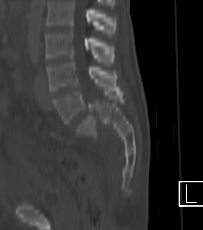

21-year old male, fall from height 8 days ago

Images attached (only CT since patient was referred to us and conventional X-rays were not digitalized).

Sagittal - Click to Magnify